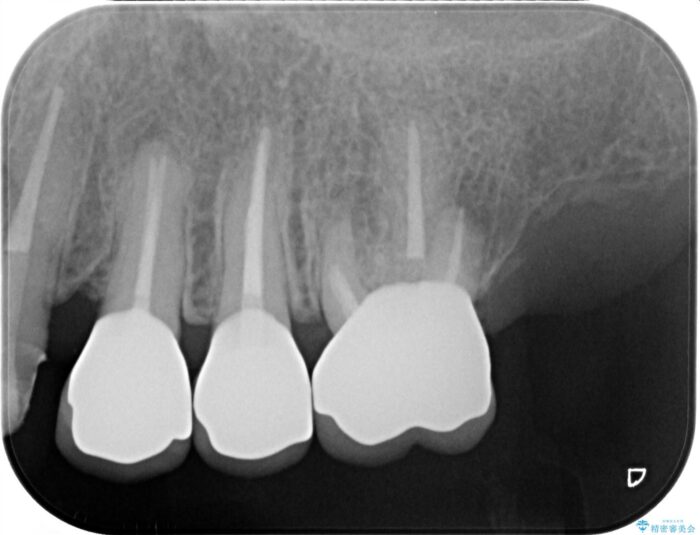

セラミッククラウンの治療は、天然の歯のような審美性を回復できることも大切ですが、精度が高くきっちりと歯ブラシを行いやすい状態を整えることで虫歯や歯周病の再発リスクを下げることも非常に大切です。